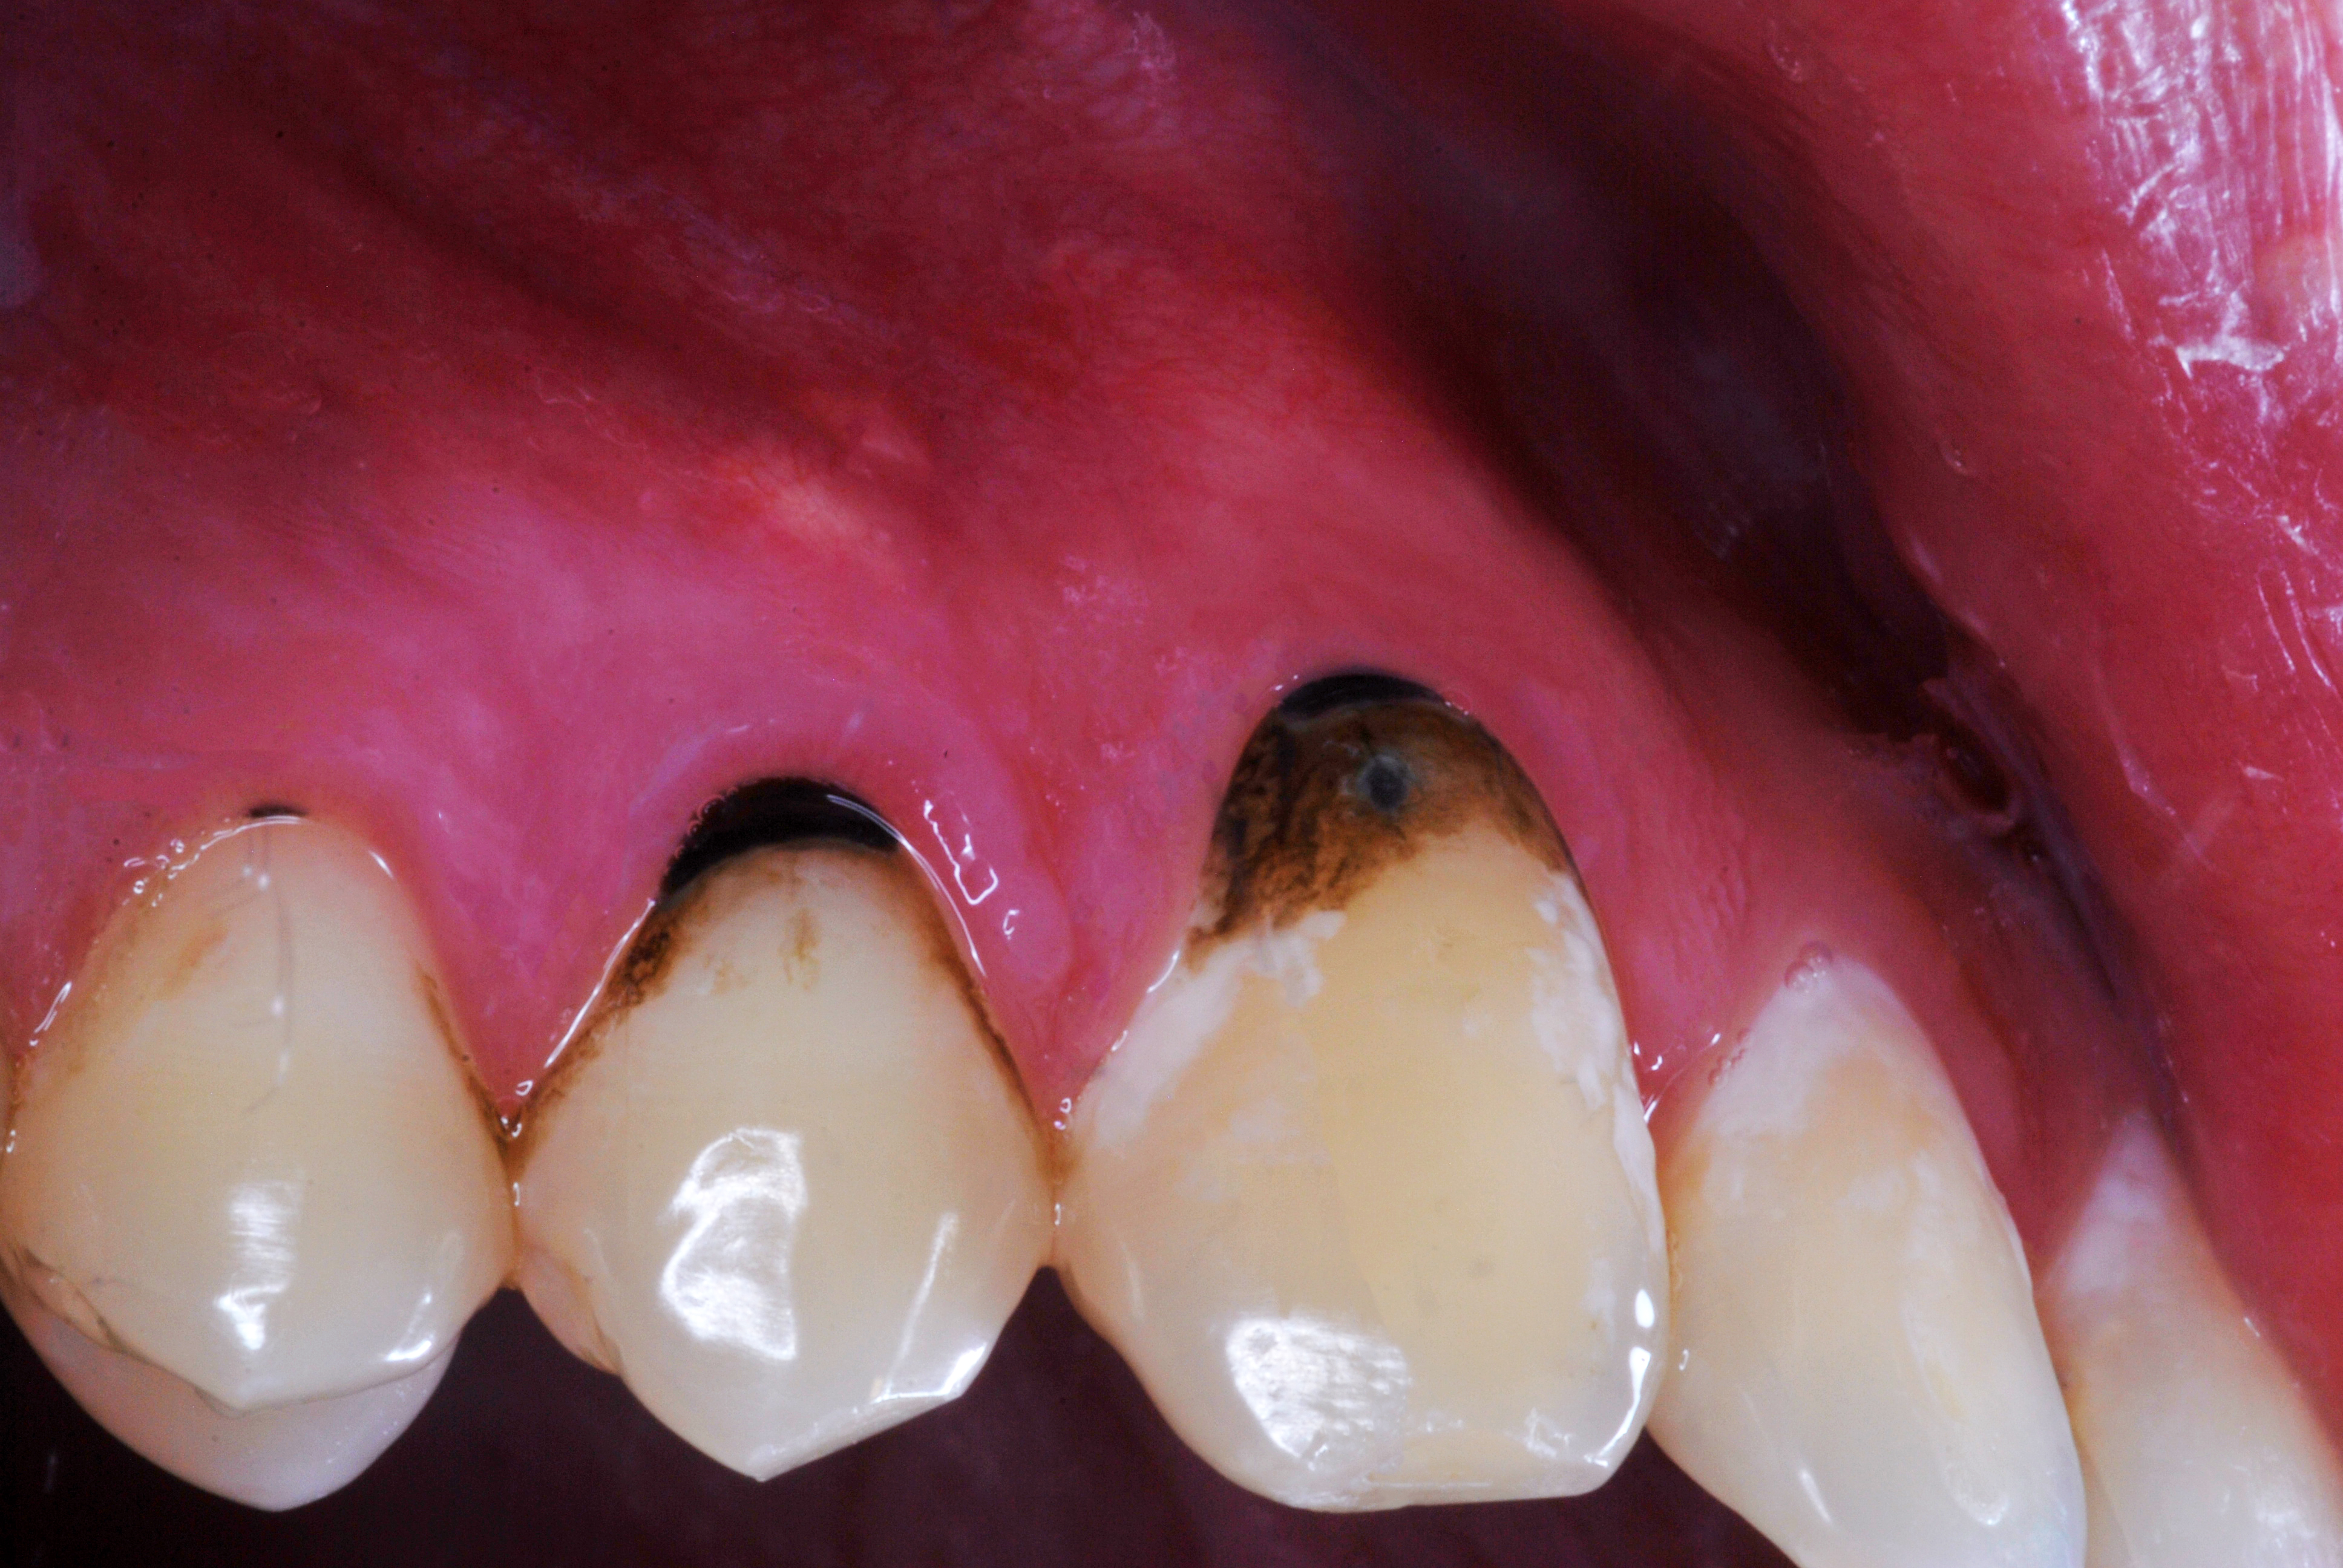

(15.) A 21-year-old patient returned for a second SDF/fluoride varnish treatment for cervical caries, 3 months after initial SDF application. The patient needed to delay restorative care for “personal reasons.”

Figure 15

(16.) A 21-year-old patient returned for a second SDF/fluoride varnish treatment for cervical caries, 3 months after initial SDF application. The patient needed to delay restorative care for “personal reasons.”

Figure 16